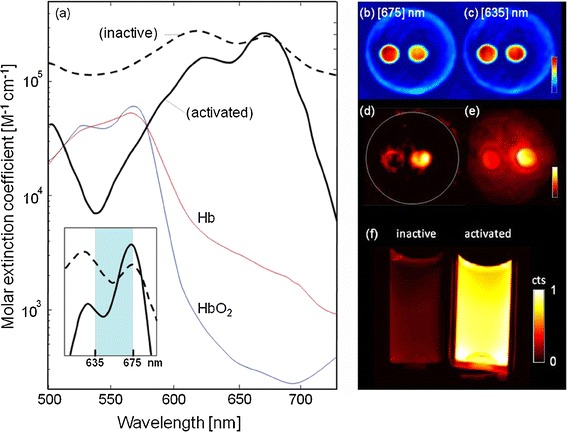

Figure 2 demonstrates basic validation measurements that summarize and explain the MSOT ability to detect probe enzymatic activation. Fig. 2a plots measurements of the spectral extinction characteristics of the inactive (dotted line) and activated (solid gray line) forms of the MMPSense™ 680 probe while the spectra of oxy- and deoxyhemoglobin is also shown for reference purposes. An enabling feature for the method developed herein, is the characteristic spectral change of the extinction (absorption) coefficient between activated and non-activated states, in the far-infrared portion of the spectrum between 635 and 675 nm, shown in greater detail in the insert of Fig. 2a.

Fig. 2.

a Measured spectral extinction characteristics of inactive (dotted line) versus activated (solid gray line) MMPSense™ 680 probe. Spectra of oxy- and deoxyhemoglobin are also shown for reference. Inset: zoom-in from the wavelength range that was used for MSOT imaging. b Optoacoustic image of phantom with MMPSense™ insertions at 635 nm excitation. Circular insertion containing activated probe is on the right while the inactive insertion is on the left. c Corresponding optoacoustic image at 675 nm excitation. d Multispectrally resolved (MSOT) image resolving the distribution of activated probe inside the phantom. e Planar (top view) fluorescence image of the phantom performed after MSOT imaging sessions, confirming fluorescence from the activated probe. f Planar fluorescence image comparing inactive (left) and active MMPSense™.

To test the methodology, the tissue-mimicking (scattering and absorbing) phantom with insertions containing activated and inactive MMPSense probe was imaged by both MSOT and epi-fluorescence. While spectral changes between active (circular insertion on the right) and inactive (insertion on the left) are not clearly distinguishable at the representative single wavelength reconstructions of Fig. 2b (made at 635 nm) and Fig. 2c (675 nm) of the phantom imaged, multispectral processing accurately reveals the different states between the left and right tubes in Fig. 2d. Fig. 2e shows a corresponding ‘top-view’ planar fluorescence image of the phantom, made after the MSOT measurements, showing strong fluorescence from the insertion containing the activated probe. Interestingly, light diffusion through the phantom causes the appearance of background diffusive fluorescence signal on Fig. 2e, which is absent from the reconstructed MSOT images of Fig. 2d due to the high-resolution three-dimensional imaging capabilities of the method, not affected by light diffusion. Finally, Fig. 2f offers an independent confirmation of the MMPSense activation by trypsin and the fluorescence signal changes observed by direct imaging of activation in two transparent tubes, without surrounding diffusive medium.